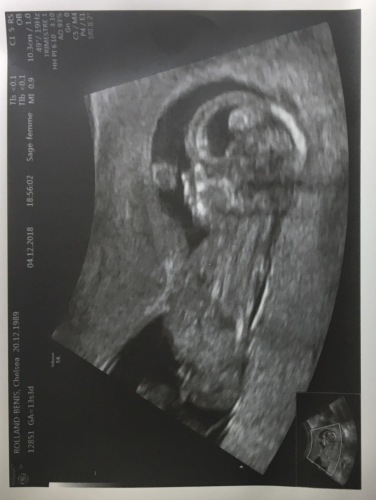

Meet baby to be.

Do you see the profile?

Due date is the early part of June 2019.